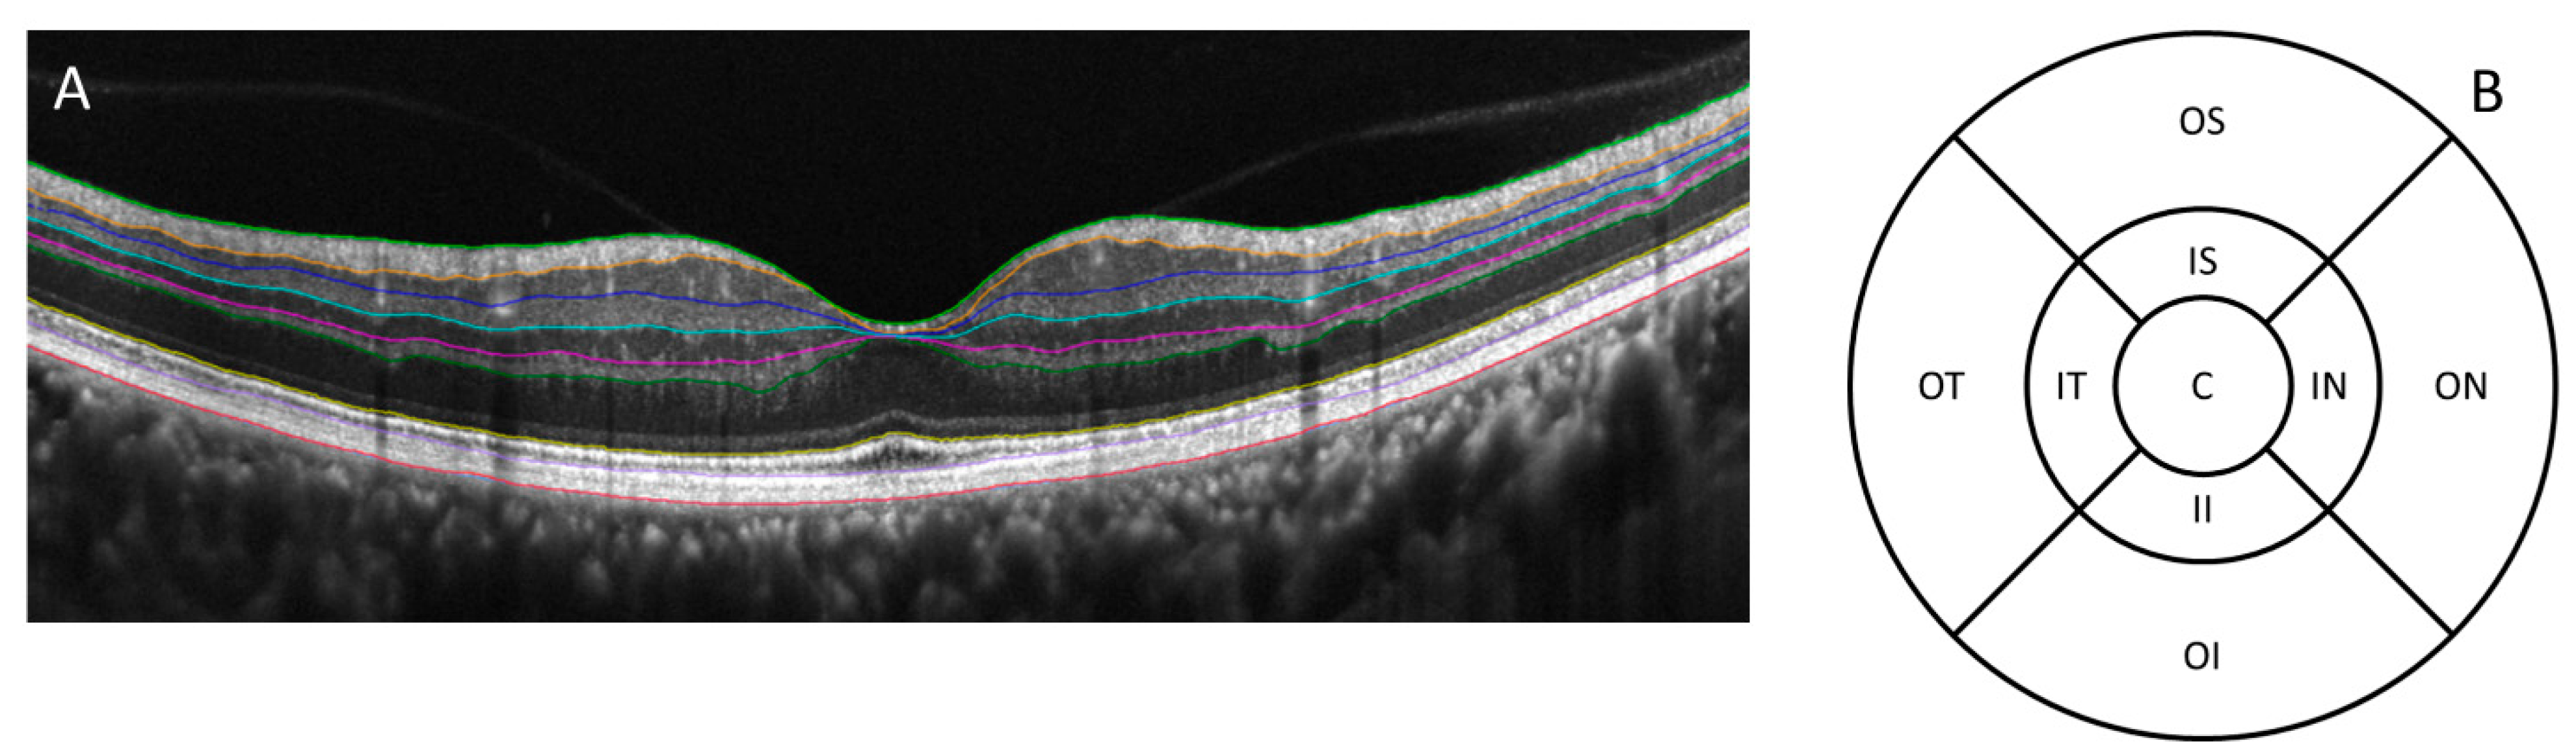

2. Methods and Materials

2.2. OCT Scans